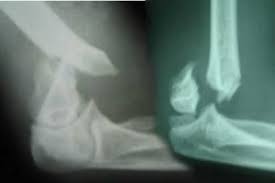

dirsek kirigi belirtileri dirsek kirigi tedavisi fizyoo